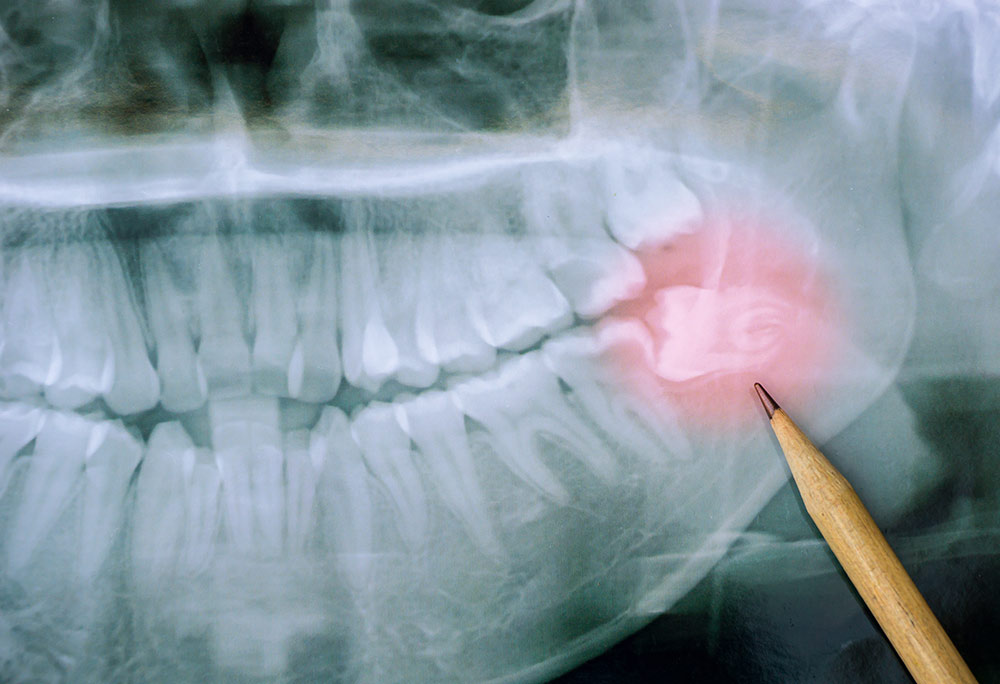

Wisdom teeth usually appear during the late teenage or young adult years. Modern human jaws often lack enough space for these teeth. Because of this, wisdom teeth frequently grow at awkward angles.

Sometimes the teeth stay trapped under the gums, causing pressure. This condition is called impaction and often needs professional attention. Many patients eventually require surgery for wisdom tooth removal for lasting relief.

Your visit usually begins with clear digital imaging of teeth. This helps the dentist clearly see each tooth position. After planning, anesthesia keeps you relaxed and thoroughly comfortable.

If the tooth is impacted, a small gum opening is made. The dentist carefully removes the tooth with very gentle movements. To make extraction less difficult, the tooth can sometimes break into fragments.